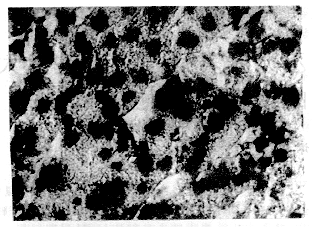

转染后第3天,肝组织地高辛标记的HBV DNA探针原位杂交结果如图1所示,可见大量棕褐色颗粒存在于肝细胞浆中,提示大量HBV DNA正在转录成相应的mRNA。

图1 HBV转基因大鼠肝脏HBV DNA探针原位杂交(400)